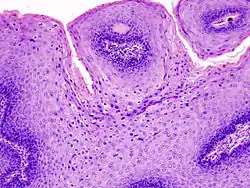

El médico puede identificar verrugas en tejido genital, que de otro modo serían invisibles, mediante la aplicación de vinagre (ácido acético) sobre áreas en que se sospeche la presencia de infección. Esta medida provoca que las áreas infectadas se tornen blancuzcas, lo que las hace más visibles, más aún si se realiza un procedimiento llamado colposcopia. Durante la colposcopia, el médico usa una lente de aumento para examinar la vagina y cérvix. En algunos casos, el doctor toma una muestra de tejido del cuello uterino (biopsia) y la examina al microscopio.